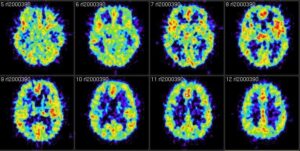

ZURIGO – Per la prima volta al mondo dei neurochirurghi svizzeri hanno effettuato un intervento al cervello con gli ultrasuoni, e pertanto senza dover aprire la scatola cranica. Lo annuncia l’Università di Zurigo, spiegando che Daniel Jeanmonod e Ernst Martin hanno applicato alla chirurgia intracranica la tecnica degli ultrasuoni focalizzati ad alta intensità, già utilizzata da anni in ginecologia e contro i tumori alla prostata.

Durante uno studio clinico, avviato nel settembre scorso, dieci adulti sono stati sottoposti all’intervento, che si è concluso con successo e senza complicazioni. Le operazioni sono state effettuate senza anestesia su pazienti totalmente coscienti e in ambulatorio.

I malati trattati soffrivano di dolori di origine neurologica, ha precisato Martin all’agenzia svizzera Ats. Una patologia che colpisce spesso le persone che hanno subito un’amputazione. Il cervello non riceve più messaggi dagli arti, i nervi inviano stimoli che danno dolori. Gli ultrasuoni – secondo gli esperti – hanno permesso di mettere a tacere questi stimoli.